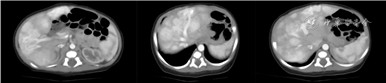

患儿女,因“生后肤色发绀25 min”入院。患儿系第2胎第1产,胎龄37+5周因“胎儿发育异常”剖宫产娩出,生后无窒息,出生体重3 310 g。母孕22周发现胎盘绒毛膜血管瘤、胎儿肝内门体静脉分流Ⅳ型。入院查体:肤色发绀,全身可见散在红色斑疹,头部、左侧肩胛骨、右前臂、背部等可见大小不等片状不规则黑色斑记,最大6 cm×3 cm,其上可见少量毛发附着,见图1A。心肺腹查体无异常,肌张力可。入院时血小板98×109/L,逐渐恢复正常。肝功能、凝血功能、血氨等无异常。肝脏超声提示肝内门体静脉分流Ⅳ型,肝脏实质回声不均。上腹部CT平扫+增强考虑门体静脉分流(Ⅳ型),腹腔干梭形膨大,肝内多发结节及斑片状异常密度影,考虑多发血管内皮细胞瘤,见图2。皮肤镜示浅表血管瘤样改变。诊断:先天性门体静脉分流(congenital portosystemic shunts,CPSS)Ⅳ型。经吸氧发绀缓解;缓慢加奶可耐受;多磺粘多糖乳膏局部护理皮肤,效果不佳,且皮疹进行性增多、增大,见图1B。日龄16 d在首都儿科研究所就诊,皮肤活检提示血管瘤,经皮肤科、介入科、儿外科综合评估后,给予口服普萘洛尔治疗,治疗3个月血管瘤数量和范围有增多、增大趋势,治疗6个月后血管瘤明显减少,见图1C、D,监测血氨、肝功能均正常。生后30 d全外显子基因回报:患儿及其父亲EPHB4基因chr7:100416271存在c.1298-5C>T杂合变异,母亲EPHB4基因chr7:100416271为野生型,见图3。